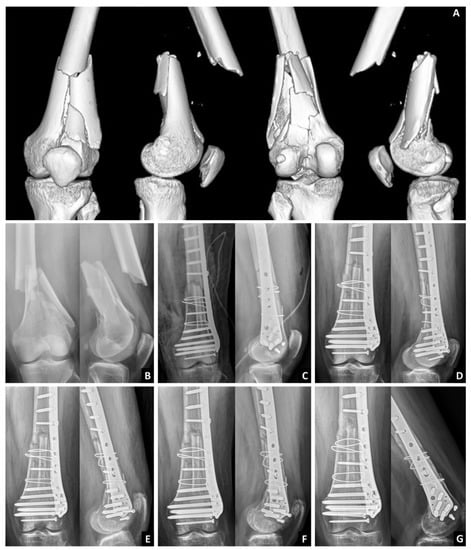

Use of an Intramedullary Allogenic Fibular Strut Bone and Lateral Locking Plate for Distal Femoral Fracture with Supracondylar Comminution in Patients over 50 Years of Age

2.1. Surgical Technique